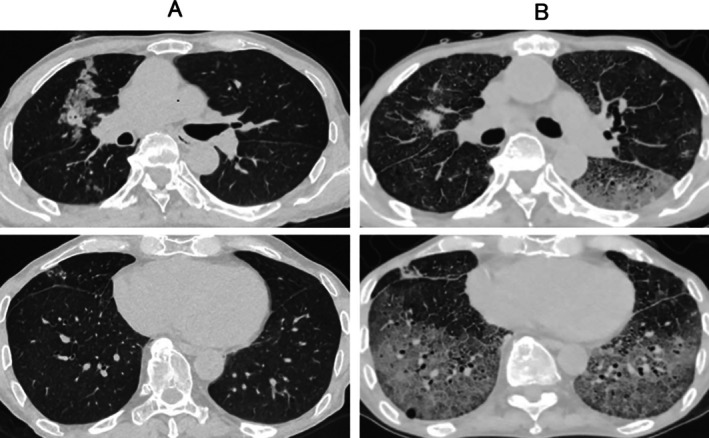

免疫检查点抑制剂(ICIs)是肺癌的基本治疗方法,但其在同种异体造血干细胞移植(alloo - hsct)后的安全性尚不清楚。我们报告一例66岁的男性,因急性淋巴细胞白血病而接受脐带血移植,后来发展为肺腺癌。开始了派姆单抗单药治疗,但患者出现了严重的类固醇难治性免疫相关肺炎,导致治疗开始56天后死亡。鉴于既往HSCT的肺癌患者使用ICI的报道很少,本病例强调了关键的安全性考虑。

Immune checkpoint inhibitors (ICIs) are essential treatments for lung cancer, but their safety following allogeneic haematopoietic stem cell transplantation (allo-HSCT) remains unclear. We report a case of a 66-year-old man who underwent umbilical cord blood transplantation for acute lymphoblastic leukaemia and later developed lung adenocarcinoma. Pembrolizumab monotherapy was initiated, but the patient developed severe steroid-refractory immune-related pneumonitis, leading to mortality 56 days after treatment initiation. Given the scarcity of reports on ICI use in lung cancer patients with prior HSCT, this case highlights critical safety considerations.